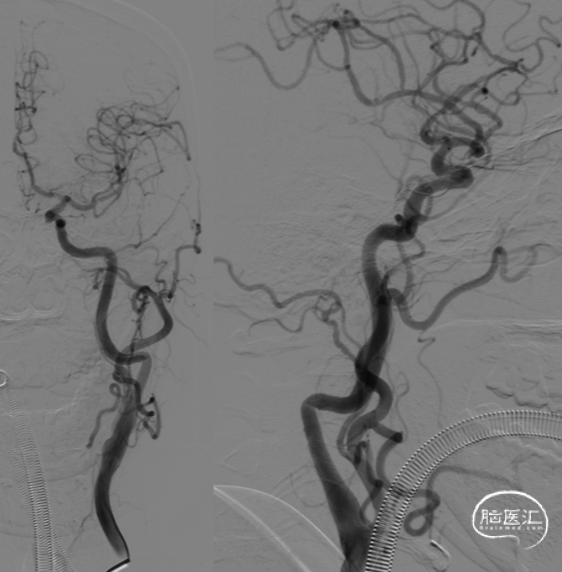

DSA(2022-01-19):

L-ICA

L-VA

R-ICA

复查DSA:左侧椎动脉V4段重度狭窄。